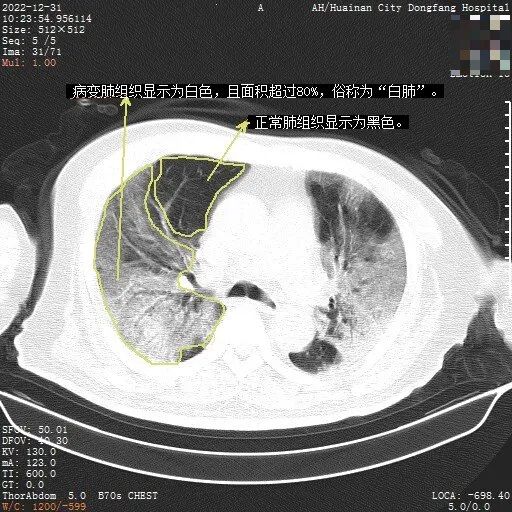

“白肺”是指肺部炎症范围广、渗出比较多,正常肺组织在CT影像上显示是黑色的,当白色的病变区域面积达到了全肺的70%-80%,就是人们口语中说的“白肺”。其实“白肺”并不是新冠病毒感染特有的表现,一些细菌感染严重时也会出现“白肺”。当出现了“白肺”,往往提示肺部病情严重,需要积极住院治疗。